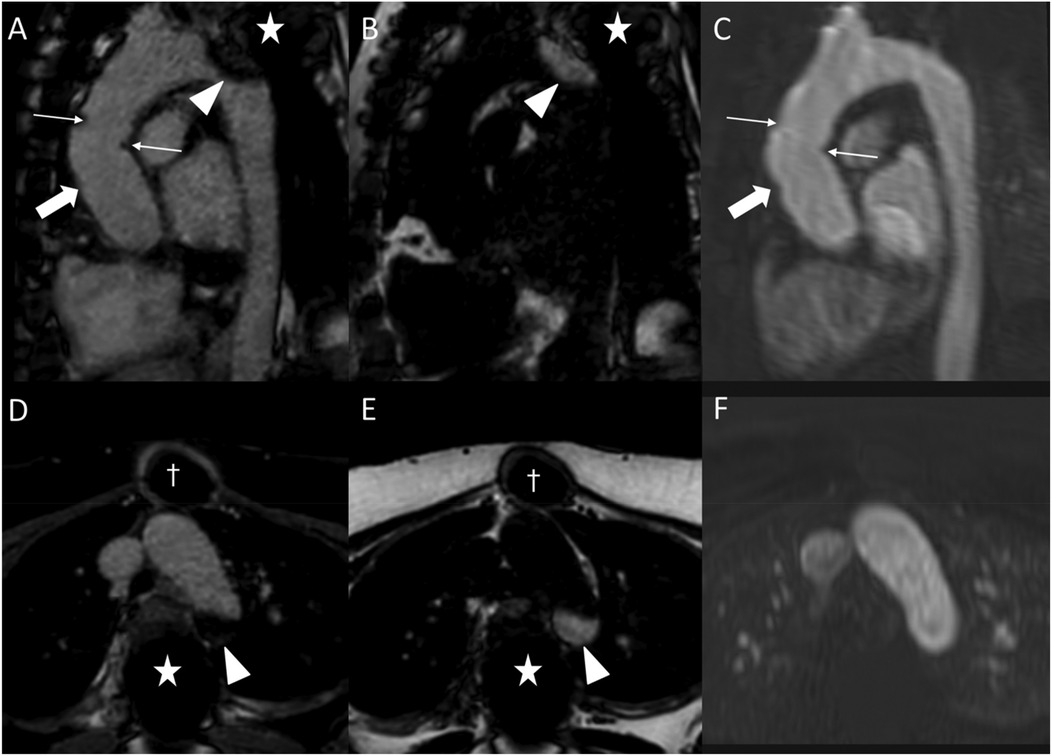

Figure 7

Fat-water separation artifact in REACT as shown in parasagittal reformations (A–C) and axial source images (D–F) in a 41-year-old female with Marfan syndrome after bentall procedure due to Stanford type A aortic dissection. While the REACT sequence [(A) and (D), water-only images; (B,E) fat-only images] enables a superior delineation of the distal anastomosis (wide arrow: mid graft, thin arrows: distal anastomosis) compared to CE-MRA (C,F), the aortic graft is apparent in both sequences. Furthermore, there is a signal loss at the aortic arch in the water-only images of REACT (arrowheads) due to spinal fusion (asterisk) with corresponding fat-only images showing a hyperintense signal, clarifying the drop-out as an artifact. Note that the susceptibility artifacts from sternal wires (daggers) do not hamper the image quality of REACT. CE-MRA, contrast-enhanced magnetic resonance angiography; REACT, relaxation-enhanced angiography without contrast and triggering.

Figure 8

REACT [(A), source image, water-only, parasagittal plane] and CE-MRA [(B), parasagittal plane] in a 46-year-old female patient following supracoronary replacement of the ascending aorta and additional stent graft of the descending aorta due to Stanford type A aortic dissection involving the aortic arch and descending aorta. Note the stronger delineation of stent strats in REACT compared to CE-MRA (thin arrows). Both REACT and CE-MRA present residual inflow (arrowheads) of the false lumen. CE-MRA, contrast-enhanced magnetic resonance angiography; REACT, relaxation-enhanced angiography without contrast and triggering.